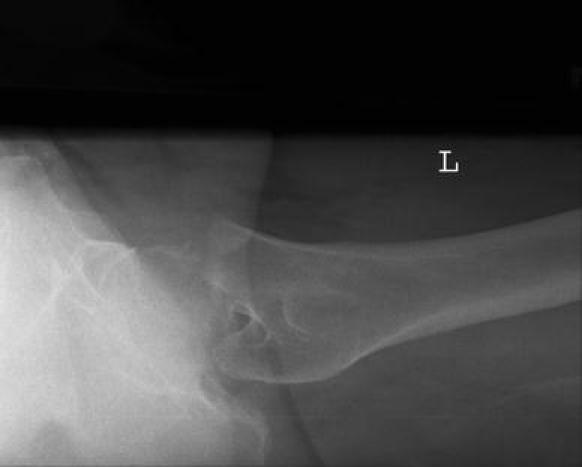

Femoral neck fracture after electrical shock injury.

A case of femoral neck fracture is reported after electrical shock injury with 300 V direct current in a 41-year old male. He had two small full thickness burns on his left heel, probably the exit wounds. A fracture after electrical shock due to musculoskeletal contractions is a very rare condition. Surgeons caring for patients with electrical injury should be aware of the possibility of skeletal injuries. Without vigilance for these injuries, delay in diagnosis may occur.